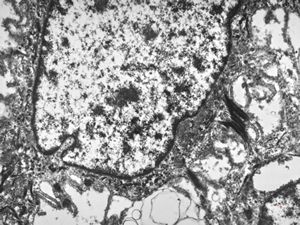

F,41y. | synovial metaplasia - capsule of implantate